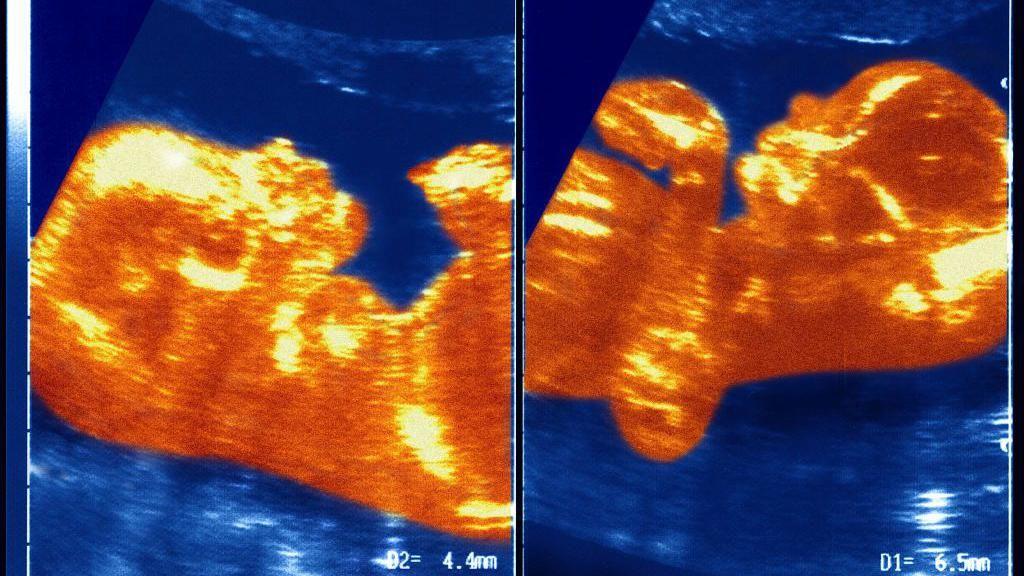

Naučnici pretpostavljaju da su u materici placente Ane Paule i njenog brata blizanca ostvarile neku vrstu kontakta, čime je obrazovana veza između krvnih sudova koji su prenosili krv dečaka u devojčicu.

„Došlo je do transfuzije krvi koju nazivamo sindrom međublizanačke transfuzije.

„U jednom trenutku, vene i arterije blizanaca su se isprepletale u pupčanoj vrpci i on je sav njegov krvni materijal preneo Ane Paule", objašnjava profesor Masijel.

„Najviše zapanjuje da je taj materijal ostao u telu ceo njen život", dodaje on.

Pretpostavlja se da su krvne ćelije njenog brata ponovo kolonizovale koštanu srž Ane Paule.

Ona je zatim počela da proizvodi krv sa XY hromozomima, dok su XX ostali u drugim delovima njenog tela.